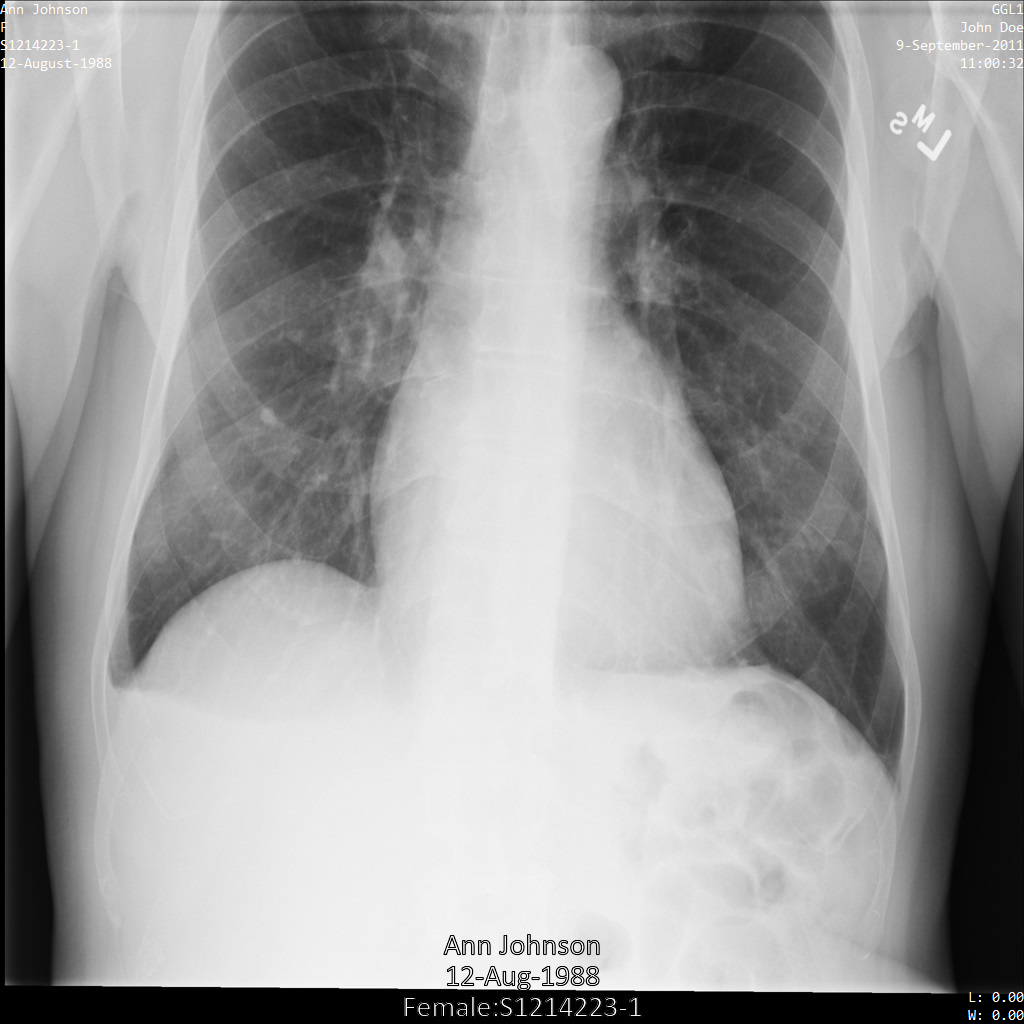

Chacune des sections suivantes fournit des exemples d'anonymisation de données DICOM à l'aide de différentes méthodes. Une sortie de l'image anonymisée est fournie avec chaque échantillon. Chaque exemple utilise l'image d'origine suivante comme entrée :

Vous pouvez comparer l'image de sortie de chaque opération d'anonymisation à cette image d'origine pour voir les effets de l'opération.

Une fois l'image envoyée à l'API Cloud Healthcare, elle apparaît comme suit. Alors que les métadonnées affichées dans les angles supérieurs de l'image ont été masquées, les informations de santé protégées qui sont incluses dans l'angle inférieur de l'image sont conservées. Pour supprimer également le texte incrusté, consultez la section Masquer le texte incrusté dans les images.